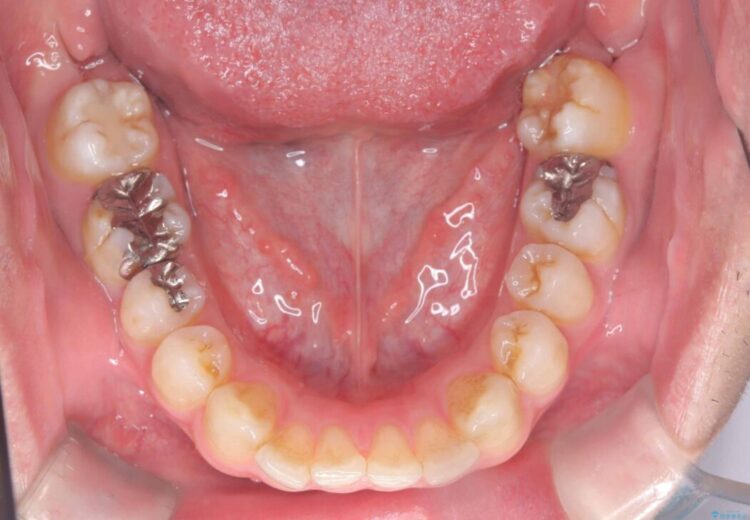

正中離開・叢生のほかに、上下の奥歯が全く咬み合わないシザーズバイトの状態も認められました。

精密検査の結果、非抜歯でインビザラインによる治療が可能と判断し、治療を行うこととしました。